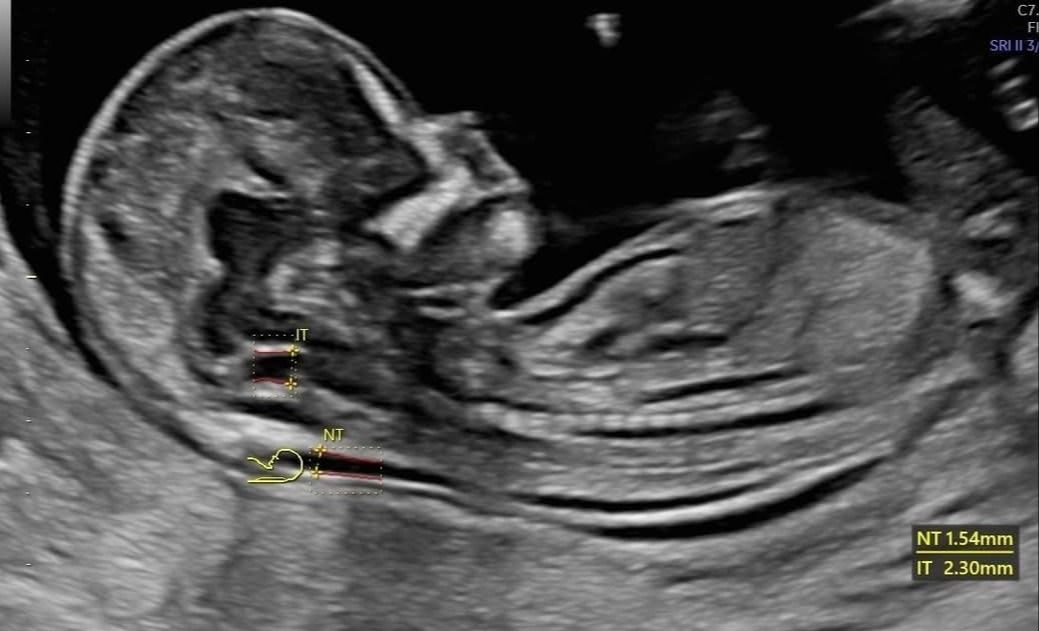

Dal 2015 al 2016 , frequenza presso U.O. Santa Maria delle Croci , Ravenna , periodo di Training di Chirurgia Laparoscopica, Endoscopica e di Isteroscopia ambulatoriale /office. In quell'anno nella stessa sede , ho  frequentato L'Ambulatorio di Diagnosi Prenatale acquisendo competenze in Ecografia Ostetrica del I-II-III trimestre.  Dopo la specializzazione ho proseguito la formazione e l'aggiornamento in particolare occupandomi dell’ Ecografia in ambito Ostetrico.

Ho acquisito "Certificate of Competence " da parte della Fetal Medicine Foundation per l'ecografia dell'11-13 settimana di gravidanza .

Da Maggio 2017 ad oggi faccio parte dello STAFF dell’Unità Operativa di Ostetricia e Ginecologia presso l’Ospedale "degli Infermi" di Faenza e dell’Ospedale "Morgagni Pierantoni "di Forli e mi occupo principalmente di Ostetricia , Gravidanza a Rischio, e dell'Ambulatorio Diagnosi Prenatale dove eseguo ecografie genetiche del I trimestre ed ecografie morfologiche e del III trimestre di gravidanza .